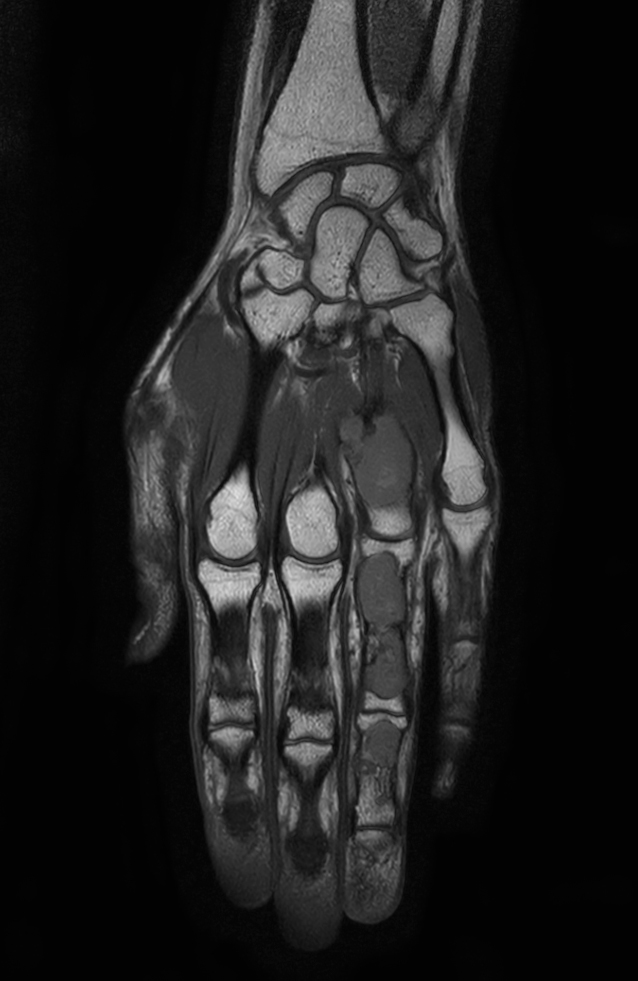

Coronal T1w mDIXON XD TSE (Water only) (with gado)

Coronal T1w mDIXON XD TSE (In Phase) (with gado)

Coronal T1w mDIXON XD TSE (Partial FatSat) (with gado)